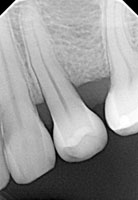

Yapılan en büyük yanlışlardan birisi 90 derece kuralını ihlal etmektir. Bu kurala radyolojide paralel çekim tekniği de denmektedir. XRAY ışını sensör üzerine dişleri/çene kemiğini geçtikten sonra 90 derecelik dik açı ile düşmelidir. Aksi halde; olduğundan daha uzun, daha kısa, daha kalın veya daha ince görünen diş/çene kesiti yansıyacaktır. Bu da kanal boyunu yanlış ölçmemize veya kanal çapı hakkında yanlış karar verilmesine sebep olabilir. Yine gelişen fiber optik teknolojisi ile bu çekim hataları %10 açı hatalarına kadar algılayıcı üzerinde düzeltilebilir. Bu özellik, algılayıcı üretim maliyetinin yükselmesine neden olur.